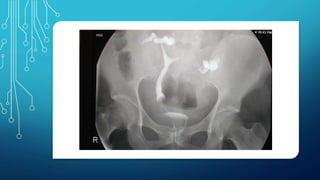

 Two widely separated uterine

cavities noted with no

passage of contrast agent

beyond the right cornua and

beyond the proximal 1/3rd of

left tube.

 Differentials

 Bicornuate uterus

 Septate uterus

Criterias used for diagnosis-

Intercornual distance

<2 cm- septate uterus.

>4 cm- bicornuate uterus.

2-4 cm- indeterminate.

Intercornual angle

<75°- septate uterus.

>105°- bicornuate uterus.

FINDINGS MORE SUGGESTIVE OF BICORNUATE

UNICOLLIS UTERUS

Intercornual angle Intercornual distance

41mm

110°

 Two widelyseparated uterine cavities noted with no passage of contrast agent beyond the right cornua and beyond the proximal 1/3rd of left tube.  Differentials  Bicornuate uterus  Septate uterus

Criterias used fordiagnosis- Intercornual distance <2 cm- septate uterus. >4 cm- bicornuate uterus. 2-4 cm- indeterminate. Intercornual angle <75°- septate uterus. >105°- bicornuate uterus.

FINDINGS MORE SUGGESTIVEOF BICORNUATE UNICOLLIS UTERUS Intercornual angle Intercornual distance 41mm 110°